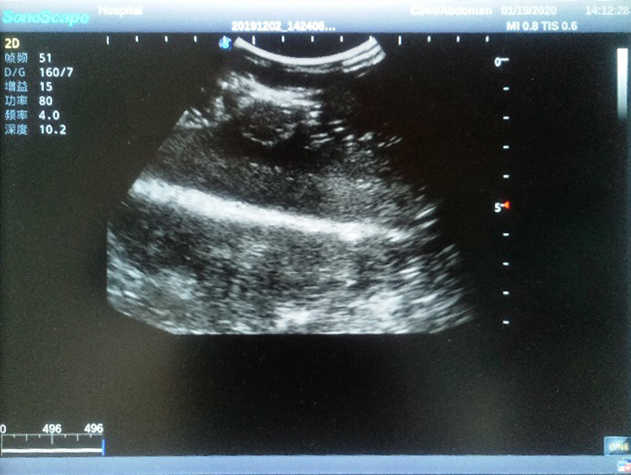

Product size(mm) 308×228×150

The Breast Ultrasound Examination Model allows users to develop and practice the skills necessary to gain proficiency in breast palpation, using ultrasound for normal and abnormal imaging and biopsy. It simulates adult female breasts with realistic size and appearance.

2)  Each model contains 8 space-occupying lesions of varying sizes, different in touch, elasticity and ultrasonogram

4) Biomimetic material allowing users to see clear and real normal tissues and space-occupying lesions that are hyperechoic, hypoechoic and isoechoic as they would see in the clinical environment